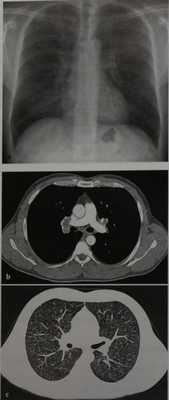

Саркоидоз с поражением легких (11-111 стадия) у мужчины 36 лет, обратившегося с жалобами на боль в груди, не сопровождавшуюся одышкой и повышением температуры тела, а На обзорной рентгенограмме грудной клетки видны двусторонняя прикорневая лимфаденопатия и мелкие узелковые затемнения в основном в верхнем и среднем легочных полях.

b, с На КТ изменения, выявленные при рентгенографии, подтвердились.